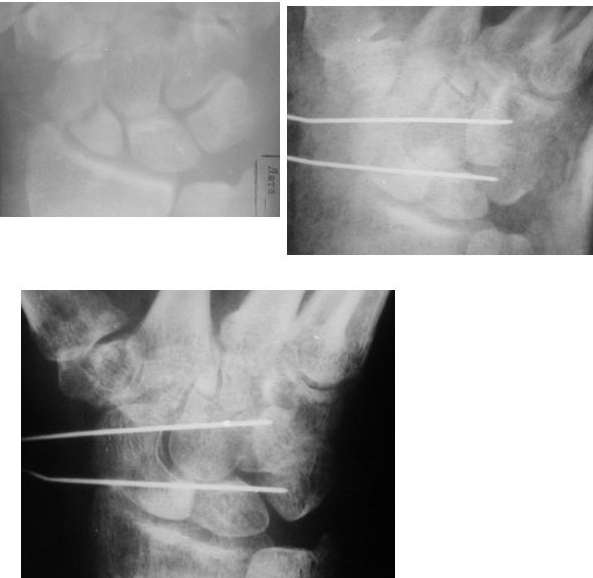

Ув. Данил! По моему мнению все-таки ложный сустав -склероз отломков (приложение), 5 мес, диастаз. Для подтверждения можно выполнить КТ кистевого сустава (формирование замыкательной пластинки, склероз концов отломков и т.д.,), а так же по КТ можно выявить сохраняется ли подвывих каких-либо костей запястья или нет. При наличии ложного сустава целесообразно будет удалить винт,обработать концы отломков, разрушив замыкательные пластинки и выполнить остеосинтез ладьевидной кости винтом с костной аутопластикой зоны псевдоартроза (либо гидроксиаппатитом...) Гипс 1,5 мес мин. Снимков найти сейчас не получилось. позже дошлю.

>остесинтез только штифтом из ауто кости!

Ув. Кирилл! Если подтвердится диагноз: ложный сустав ладьевидной кости, то штифтование аутокостью может быть неэффективным в 30% (Ашкенази 1990, Герасимов 1976 и т.д.). Это связано с тем, что в данном случае крайне важно обеспечить стабильность отломков до наступления консолидации в зоне псевдоартроза - т.е. приблизительно 3 - 8 мес, в случае штифтования аутокостью пациенту прийдется находиться в гипсе весь этот срок, что значительно скажется на функции кистевого сустава. Нужно еще учесть, что на этой ладьевидной кости уже было осуществленно оперативное вмешательство, и повторная операция в таком виде и длительная иммобилизация значительно увеличит риск аваскуллярных изменений в ладьевидной кости.Если выполнить остеосинтез ладьевидной кости винтом с костной аутопластикой зоны псевдоартроза, то срок иммобилизации составит 1,5 - 3 мес., что, вероятно, более благоприятно для функции кистевого сустава.